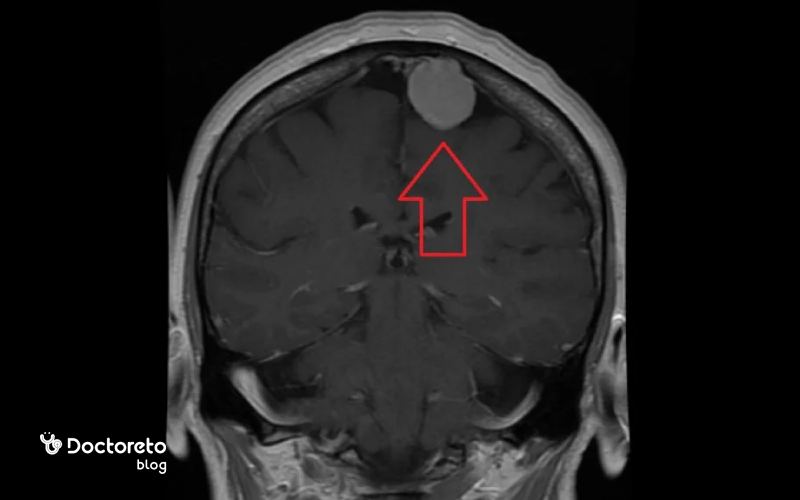

در مراحل اولیه، تومور مغزی بدخیم معمولاً اندازهای کوچک دارد و ممکن است تنها بخش محدودی از بافت مغز را درگیر کند. در تصاویر ام آر آی و سی تی اسکن، این نوع تومور بهصورت تودهای کوچک با تراکم متفاوت نسبت به بافت طبیعی مغز دیده میشود. در این مرحله معمولاً ورم یا فشار شدیدی روی نواحی اطراف مغز وجود ندارد و بیمار ممکن است تنها علائم خفیفی مانند سردردهای گهگاهی یا اختلال تمرکز را تجربه کند. گاهی در ضایعات کوچک اما شدیدا پرخطر علائم شدید است. تشخیص زودهنگام در این مرحله اهمیت زیادی دارد، زیرا درمان مؤثرتر و کمتهاجمیتر است و شانس بهبودی افزایش مییابد.

پزشکان با مقایسه عکسهای اولیه و آزمایشهای تکمیلی، نوع دقیق تومور را مشخص میکنند. در صورت شروع بهموقع درمان، احتمال کنترل رشد تومور و جلوگیری از گسترش آن به سایر بخشهای مغز بسیار بیشتر خواهد بود.